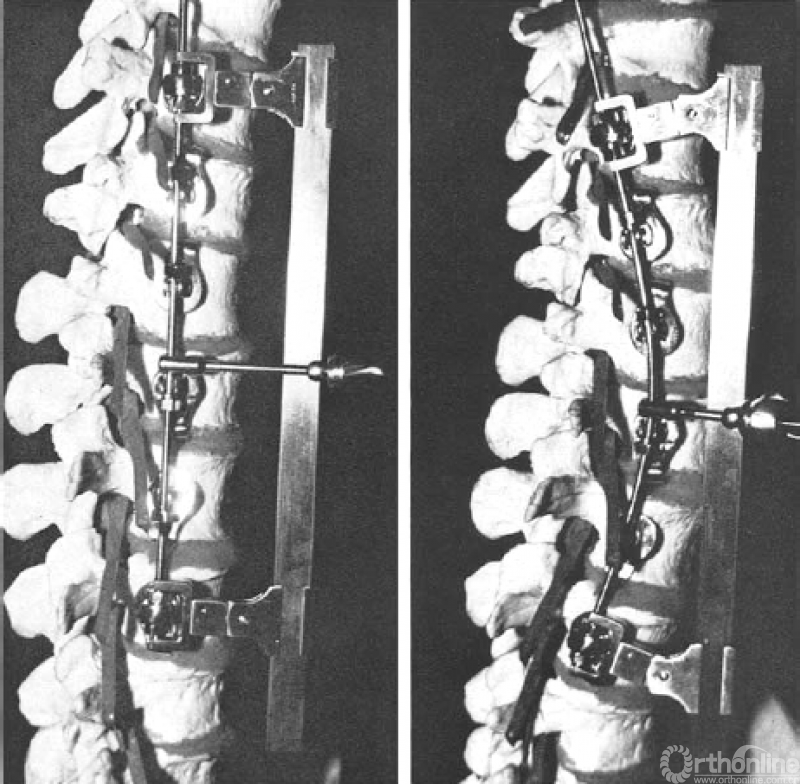

脊柱前路融合内固定技术用于治疗部分类型的青少年特发性脊柱侧凸至今已有五十多年历史。Dwyer等人[1]在1964年首先对其进行了描述。1976年Zielke等人[2]对其进行了改进,用金属棒代替了连接椎体螺钉的线缆,并提出了腹侧去旋转脊柱融合技术(VDS,Ventrale Derotation Spondylodesse),该器械操作有效地矫正了冠状面脊柱侧凸,改善了顶椎去旋转。

图1. 1976年Zielke等人提出腹侧去旋转脊柱融合技术